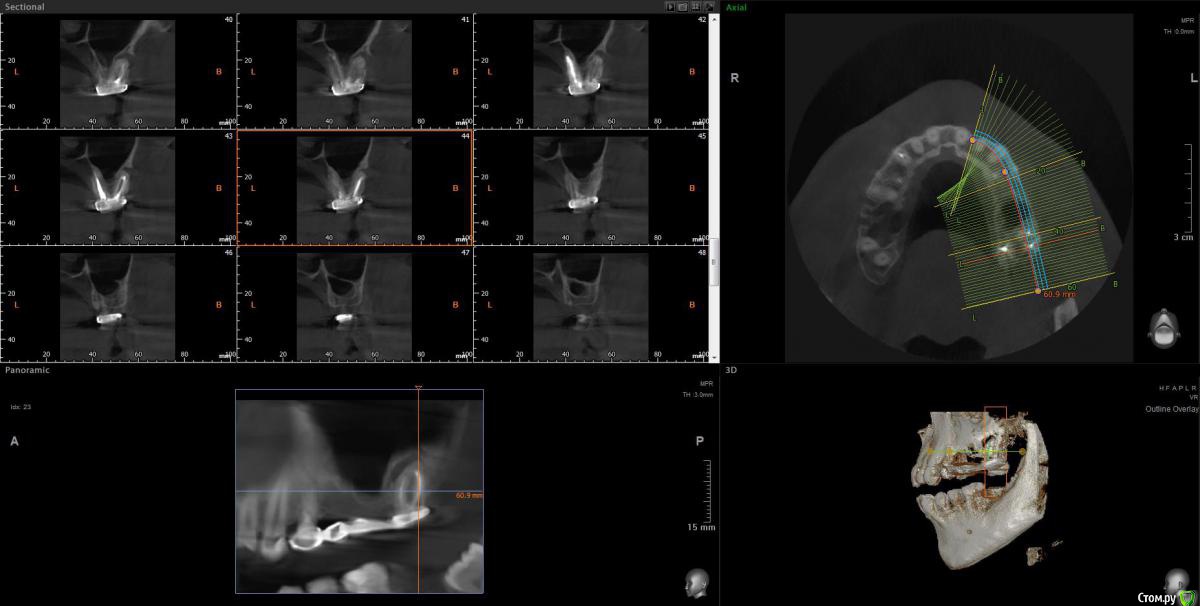

Ботинок Опубликовано 25 июля, 2020 Поделиться Опубликовано 25 июля, 2020 (изменено) Здравствуйте, Спасибо за ваше время для просмотра моей КТ. Речь про 27ой зуб https://drive.google.com/file/d/1yeLfeXNm_Ex4w3dMc1R1VGEqdMZLexYT/view?usp=sharing Жду ответов Изменено 25 июля, 2020 пользователем Ботинок Ссылка на комментарий